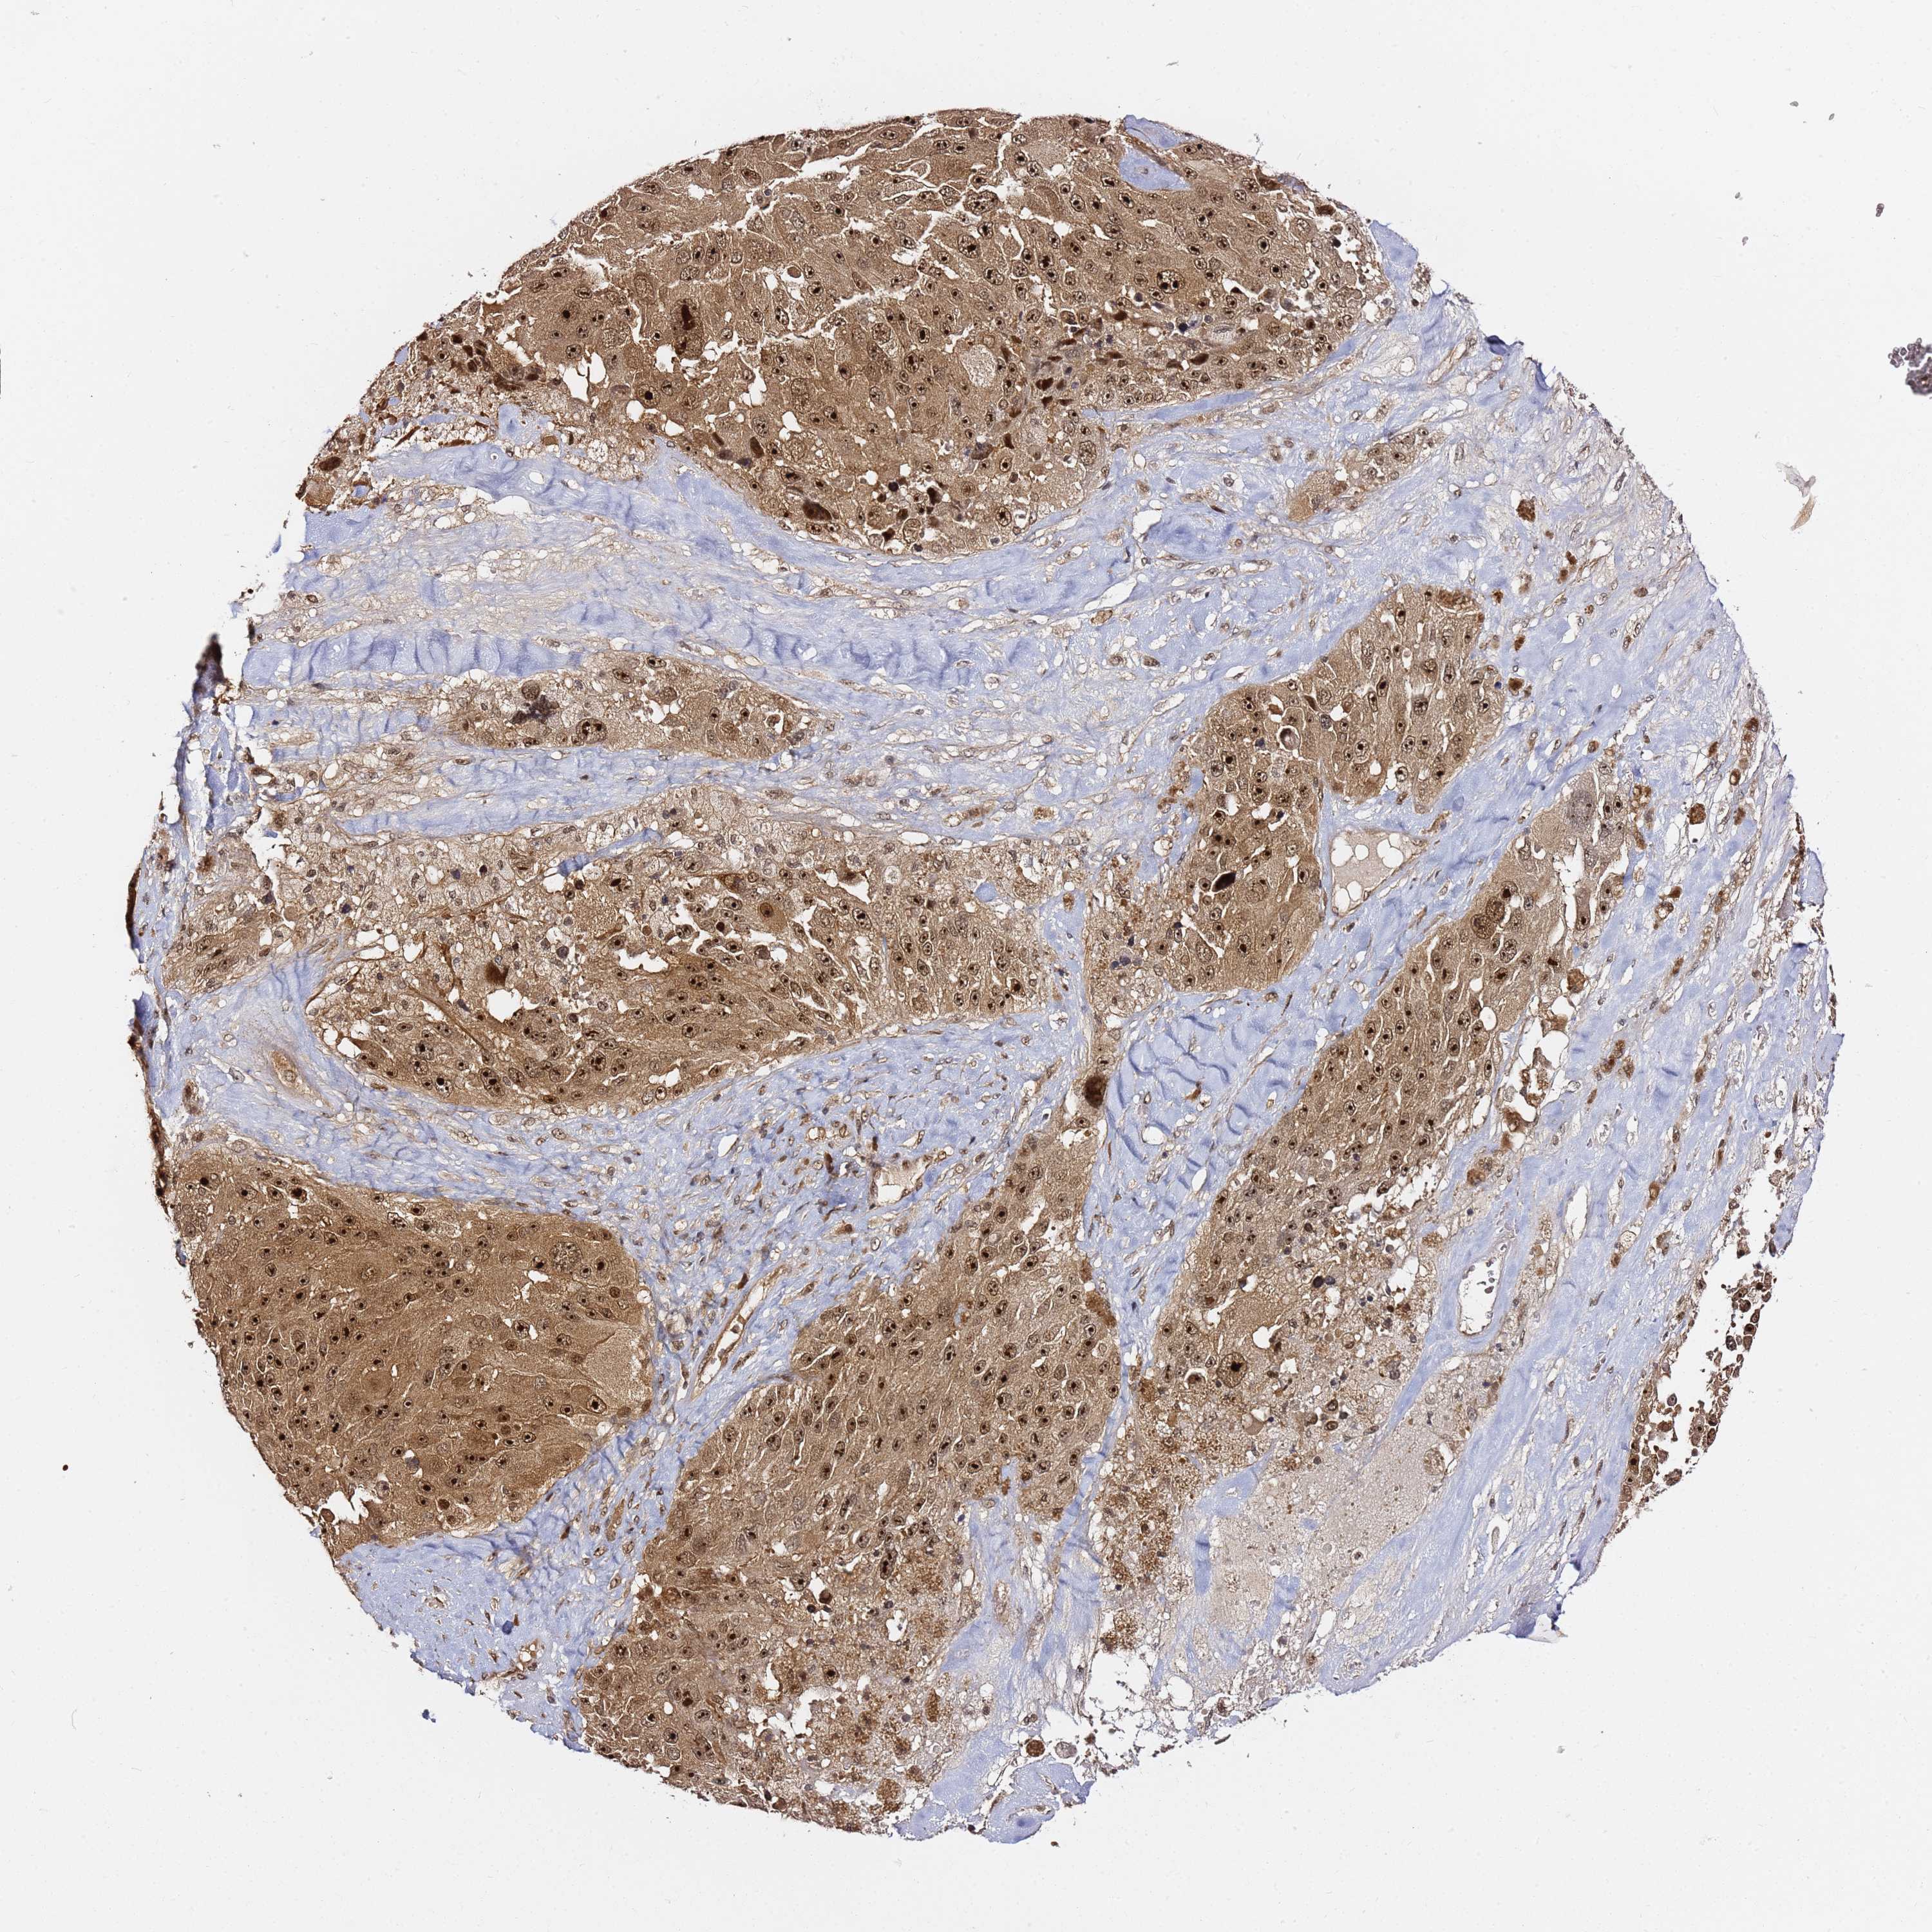

MELANOMA - Protein expressioni

A mouse-over function shows sample information and annotation data. Click on an image to view it in a full screen mode. Samples can be filtered based on level of antibody staining by selecting one or several of the following categories: high, medium, low and not detected. The assay and annotation is described here.

Note that samples used for immunohistochemistry by the Human Protein Atlas do not correspond to samples in the TCGA dataset.

Antibody stainingi

Antibody staining in the annotated cell types in the current human tissue is reported as not detected, low, medium, or high, based on conventional immunohistochemistry profiling in selected tissues. This score is based on the combination of the staining intensity and fraction of stained cells.

Each image is clickable and will lead to virtual microscopy that enables deeper exploration of all samples and also displays staining intensity scores, fraction scores and subcellular localization as well as patient and tissue information for each sample.

Antibody HPA045780

Staining

High

Medium

Low

Not detected

Intensity

Strong

Moderate

Weak

Negative

Quantity

>75%

75%-25%

<25%

None

Location

Nuclear

Cytoplasmic/membranous

Cytoplasmic/membranous,nuclear

Malignant melanoma, Metastatic site